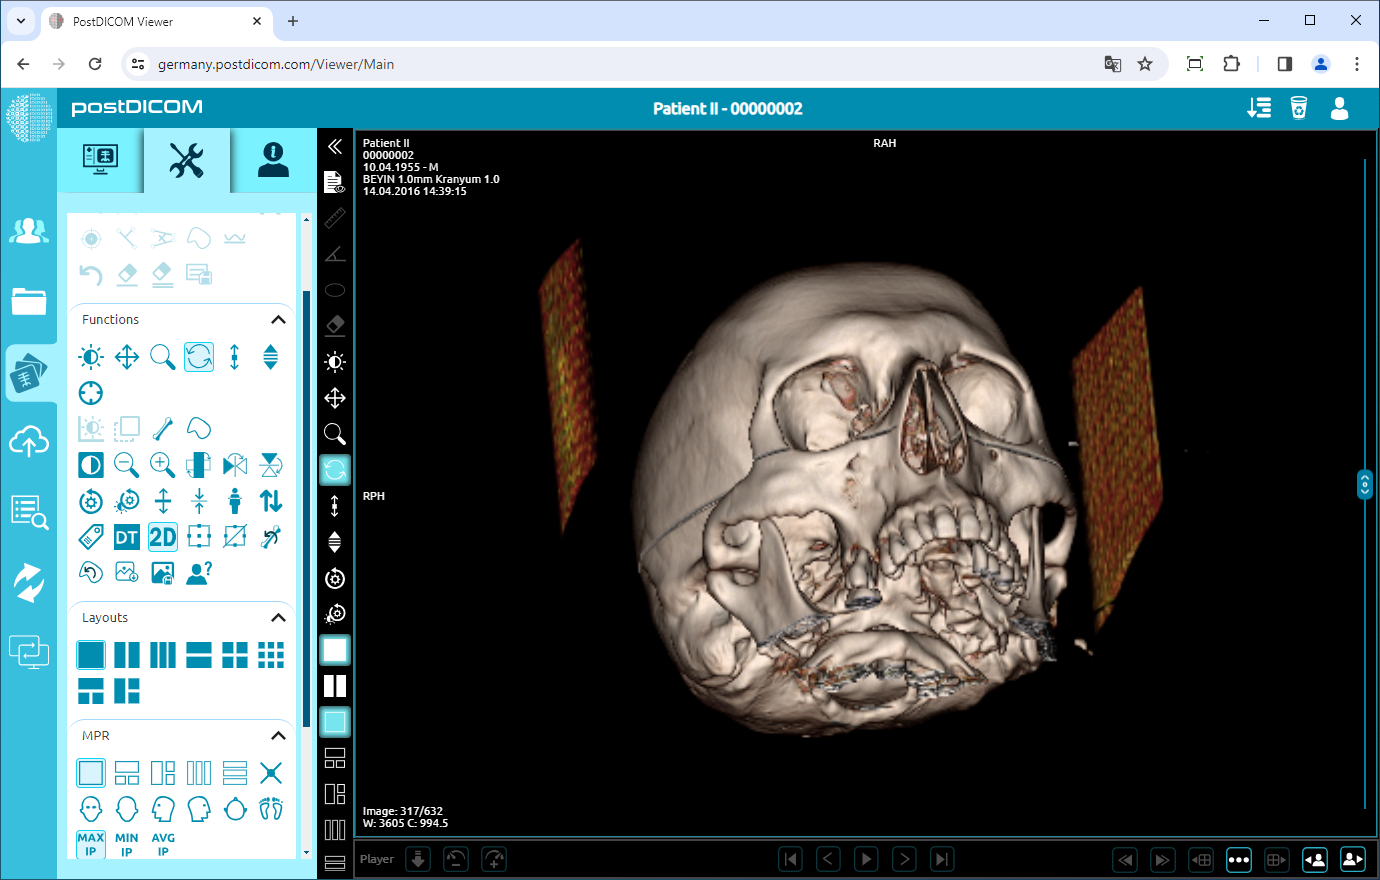

Once you have clicked the icon, the 3D image appears on the viewport. You can use most of the functions on the 3D image. The active functions will be shown colored and the inactive functions will be shown dimmed in the functions field.